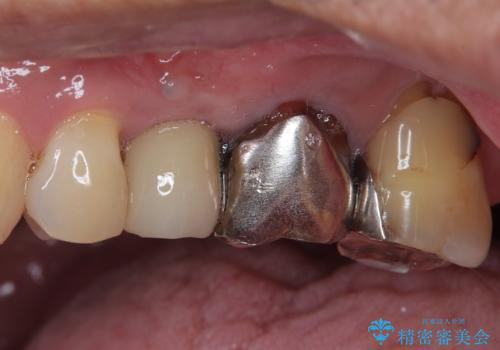

- 口を開けたときに目立ってしまう銀歯をセラミックに替えたいとのことで来院された患者様です。

以前むし歯治療を受けたときは時間がなかったため、近医で銀歯を入れたようですが、周囲の目線が気になるとのことでフルジルコニアクラウンにて補綴することとしました。